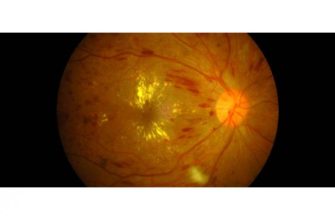

Retinopathy is a condition that affects the retina